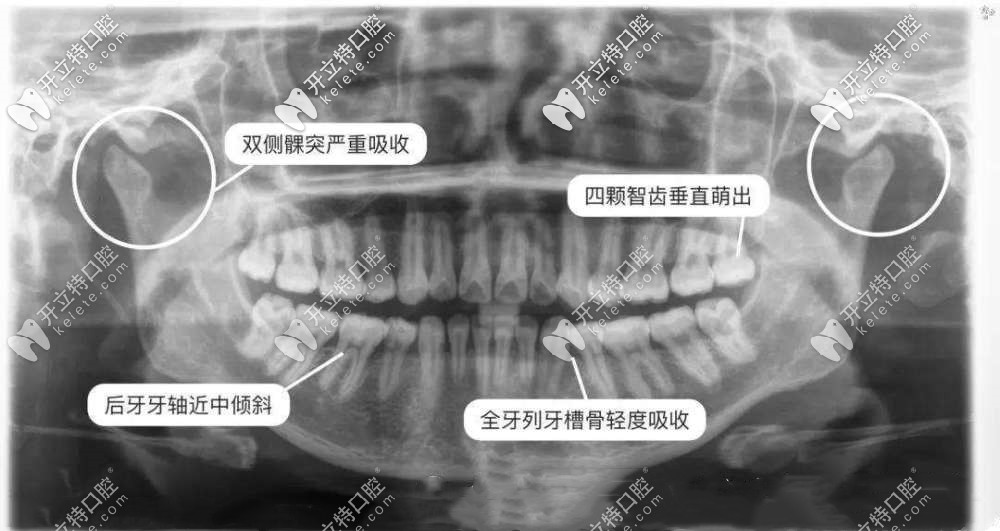

拍牙齒x光片能看出智齒的情況、齲壞的情況等,而一般拍一次x光片的價(jià)格根據(jù)類型不同,其價(jià)格也在在幾十到幾百不等,下面小編會(huì)給大家詳細(xì)介紹下,感興趣的小伙伴們快來(lái)看看吧。

口腔中的牙片由以下幾種組成:小牙片、全景片,頭顱側(cè)位片、牙科CT,不同牙片的區(qū)別主要是看的牙病不同,比如小牙片看單個(gè)牙齒情況,頭顱側(cè)位片用于正畸,全景片和牙科CT做種植牙用。